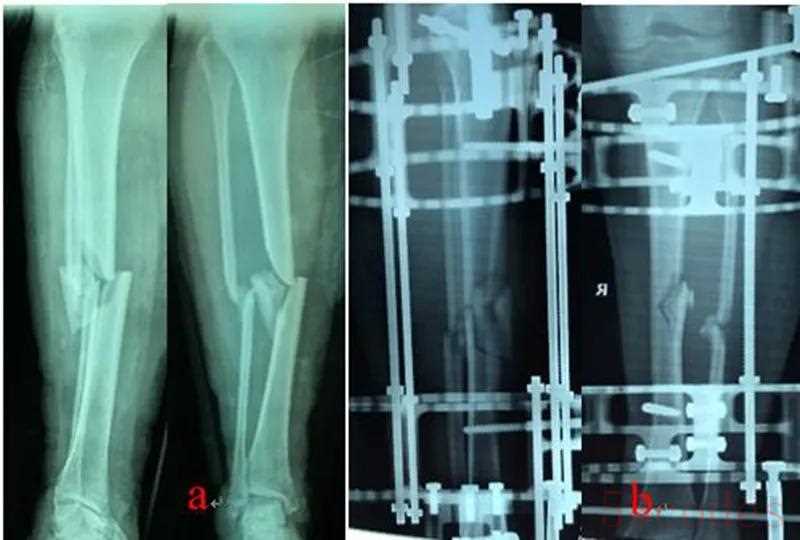

乔锋等利用自主研发的3D打印骨科外固定架(QF)和数字六轴外架(QSF)治疗胫骨骨折,获得良好的临床疗效。3D打印骨科外固定架具有自动复位骨折功能,4根螺纹连接杆与骨的轴线平行,通过旋拧调节螺母,调节两个固定环之间的距离,实现对骨折断端轴向应力的调节和固定方式的转换,早期坚强固定,中期加压固定,后期弹性固定。复位过程无需透视,不依赖医生经验,手术时间短,可以不用麻醉,术后即可完全负重下地行走,复位精确,固定合理,操作简便。数字六轴外架QSF配套软件基于CT数据,与国际同类产品比较,复位精确,固定牢靠,操作简便,学习曲线短。

图1:QF治疗胫腓骨骨折

图2:QSF治疗胫腓骨骨折